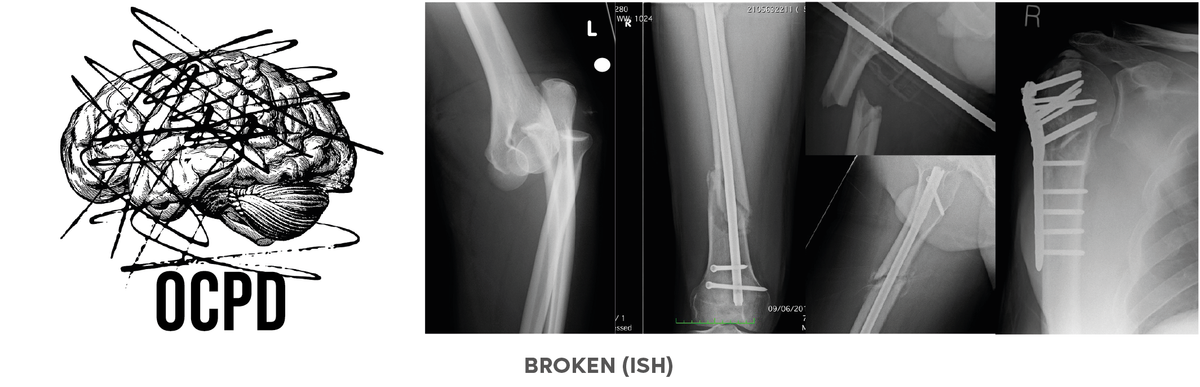

The broken (both mental health and physical) is a little more complicated and although I’ll get into both in more detail at some point, a key contributor to the afore-mentioned ‘bitterness’ is a constant battle with performance anxiety and impostor syndrome, both of which I rarely, if ever, win.